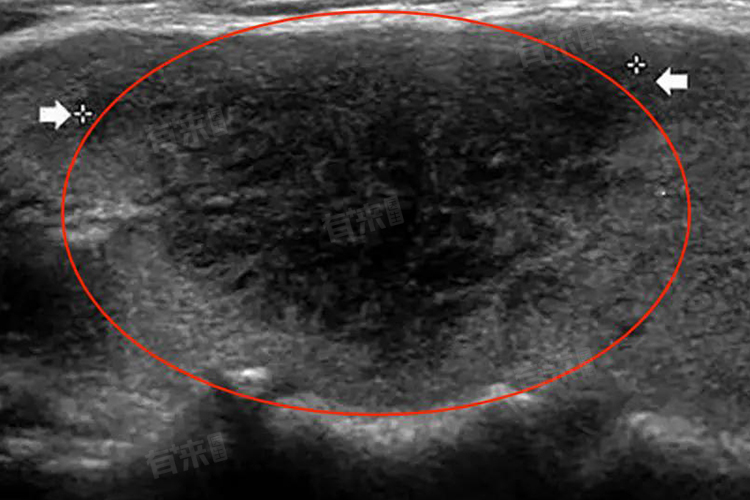

低回声结节是在超声检查中发现的一种影像表现,具体指的是在超声图像中,病变部位的回声强度低于周围正常组织的结节状病变,结节通常提示存在实质性病变,可能的原因包括炎症、肿瘤、良性增生等。

- 恶性结节:形态多不规则,边界不清晰,包膜不完整,内部回声不均匀,可伴有钙化或液化坏死,纵横比常大于1,血流信号可能丰富。